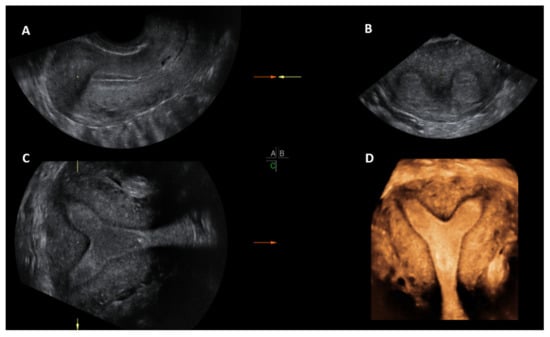

When the render mode is selected, a region of interest (ROI) box will appear on the screen. The ROI box should be manipulated so that it covers the endometrial cavity in its entirety. The green line of the ROI box indicates the direction of rendering and this should ideally be placed on top. Final adjustments can be made, such as curving the ROI box, along the curvature of the endometrial cavity and applying different render options, including Omniview, Volume Contrast Imaging (VCI) and HD live, which produces a more realistic image. Once the operator is satisfied with the 3D image, this can be enlarged and can correctly classify the type of CUA. The entire volume and individual image can be saved for later analysis. [18]. The post-processing of the stored image can be performed as described above on the ultrasound machine itself (commonly done) or using ‘4D view’ software in a computer (Figure 5).

Figure 7. 3D multiplanar view with rendering box using 4D view software: Green line of the rendering box placed on top and at the level of endometrial cavity in the longitudinal plane (A); transverse plane (B), Coronal plane (C) and rendered coronal view of uterus in the bottom right corner (D).